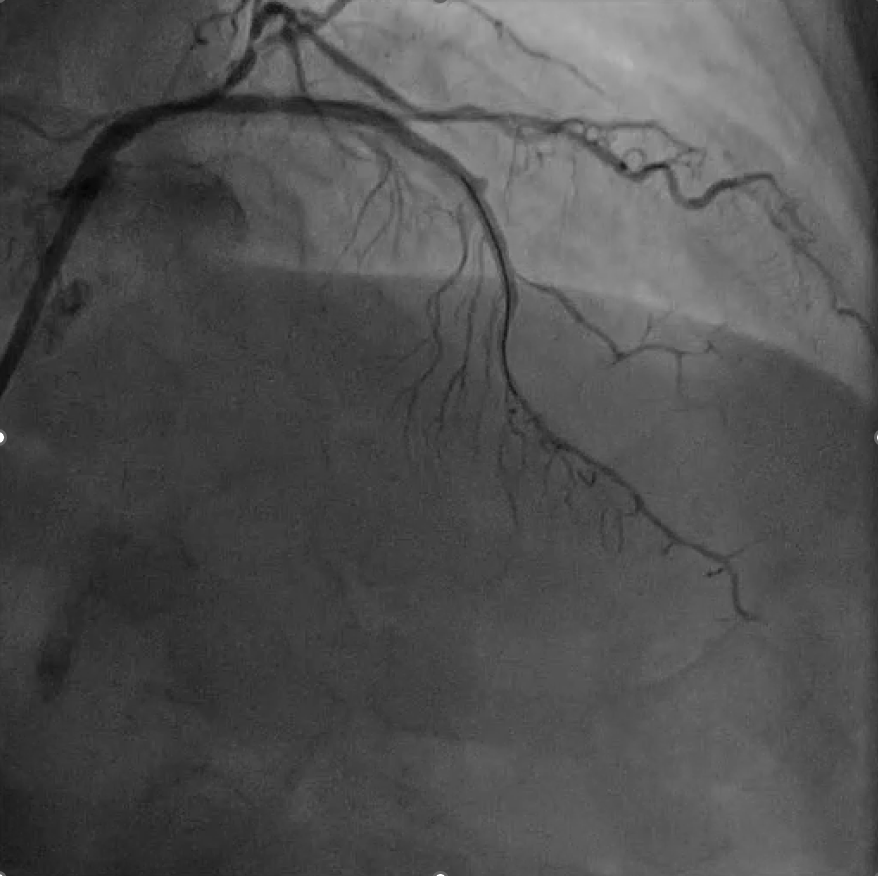

该患者为弥漫性重度钙化冠状动脉病变,在介入治疗过程中突发微导管头端断裂,病情紧急,处理难度极高。面对突发状况,团队临危不乱,凭借扎实的技术基础与丰富的术中应变经验,果断启用先进介入策略,精准定位并顺利取出断裂导管,术中未发生任何并发症,最终成功完成支架植入,恢复冠脉血运(图7-8)。

图7.微导管头端断裂图

图8.冠脉血运重建

李闯医生在报告中详细还原了手术全过程,逐层解析每一环节的技术选择与判断依据,展现出临床团队严谨务实、稳中求进的专业素养。大会主席Dr. Andrejs Erglis教授对手术的技术难度给予充分肯定,并高度评价了团队在高风险情境下的处理策略与结果。汇报结束后,李闯医生收获了来自国际同仁的热烈掌声与“Good Case”的高度赞誉。